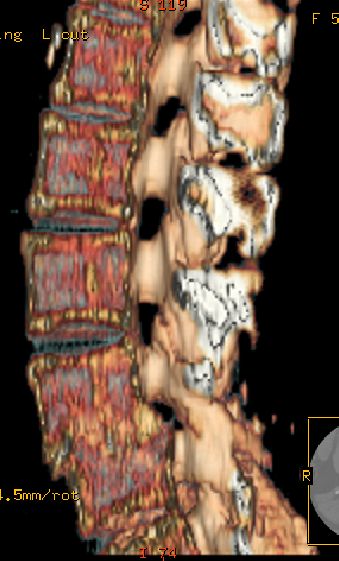

以下是引用余辉在2007-9-4 21:00:00的发言:[br]椎体棘突有点异常(像是被切割了),不知有否手术史,如椎体融合术等。单纯的退行性变可以出现椎间隙变窄,但同时一般会出现椎体上下缘的硬化增生,且椎体间完全融合的机率更小,本例椎体完全融合且椎体上下皮质缘破坏掉了,如果没有手术史,就应该考虑椎间盘炎性病变了,且椎体棘突及棘间韧带的变化也并不是不支持这个,多数小关节也融合了,且其形态也容易让人联想到如强脊炎及类风关等病变。[br][br][本贴已被 余辉 于 2007-9-4 21:03:55 修改过]

以下是引用chry3在2007-9-4 20:42:00的发言:[br]椎间盘病史?是什么样的病史,无双下肢放射痛,那就不是椎间盘突出了。是感染、什么性质的?[br]从图象看椎间隙消失,椎间盘组织未见,锥体滑脱是因为椎间盘溶解造成的[br]l4、5椎体骨质结构未见异常,l5上缘是l4的长期压迫所致[br]还是考虑椎间盘感染,结核。[br]